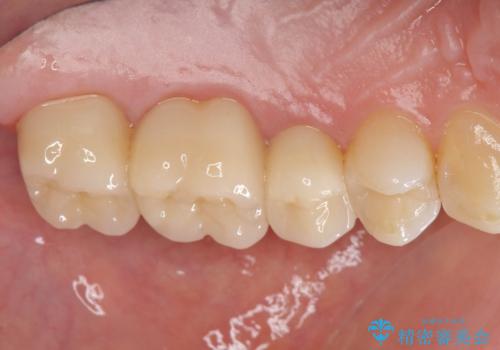

銀歯を丁寧に除去すると、銀歯の下で虫歯の再発やセメントの劣化が確認されたので、拡大鏡・マイクロスコープを用いて虫歯のみを丁寧に取り除いたのち、精密なセラミッククラウンの製作を進めます。

- 47.3万円(ジルコニアクラウン×3・仮歯×3・セラミックインレー×1)費用は治療当時の料金となります

拡大鏡・マイクロスコープを用いて虫歯を丁寧に除去することで、健全な歯質や神経を守ることにつながります。